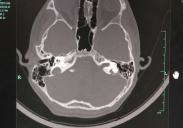

3. 影像学检查 CT,显示双侧前庭导水管扩大。

大前庭CT